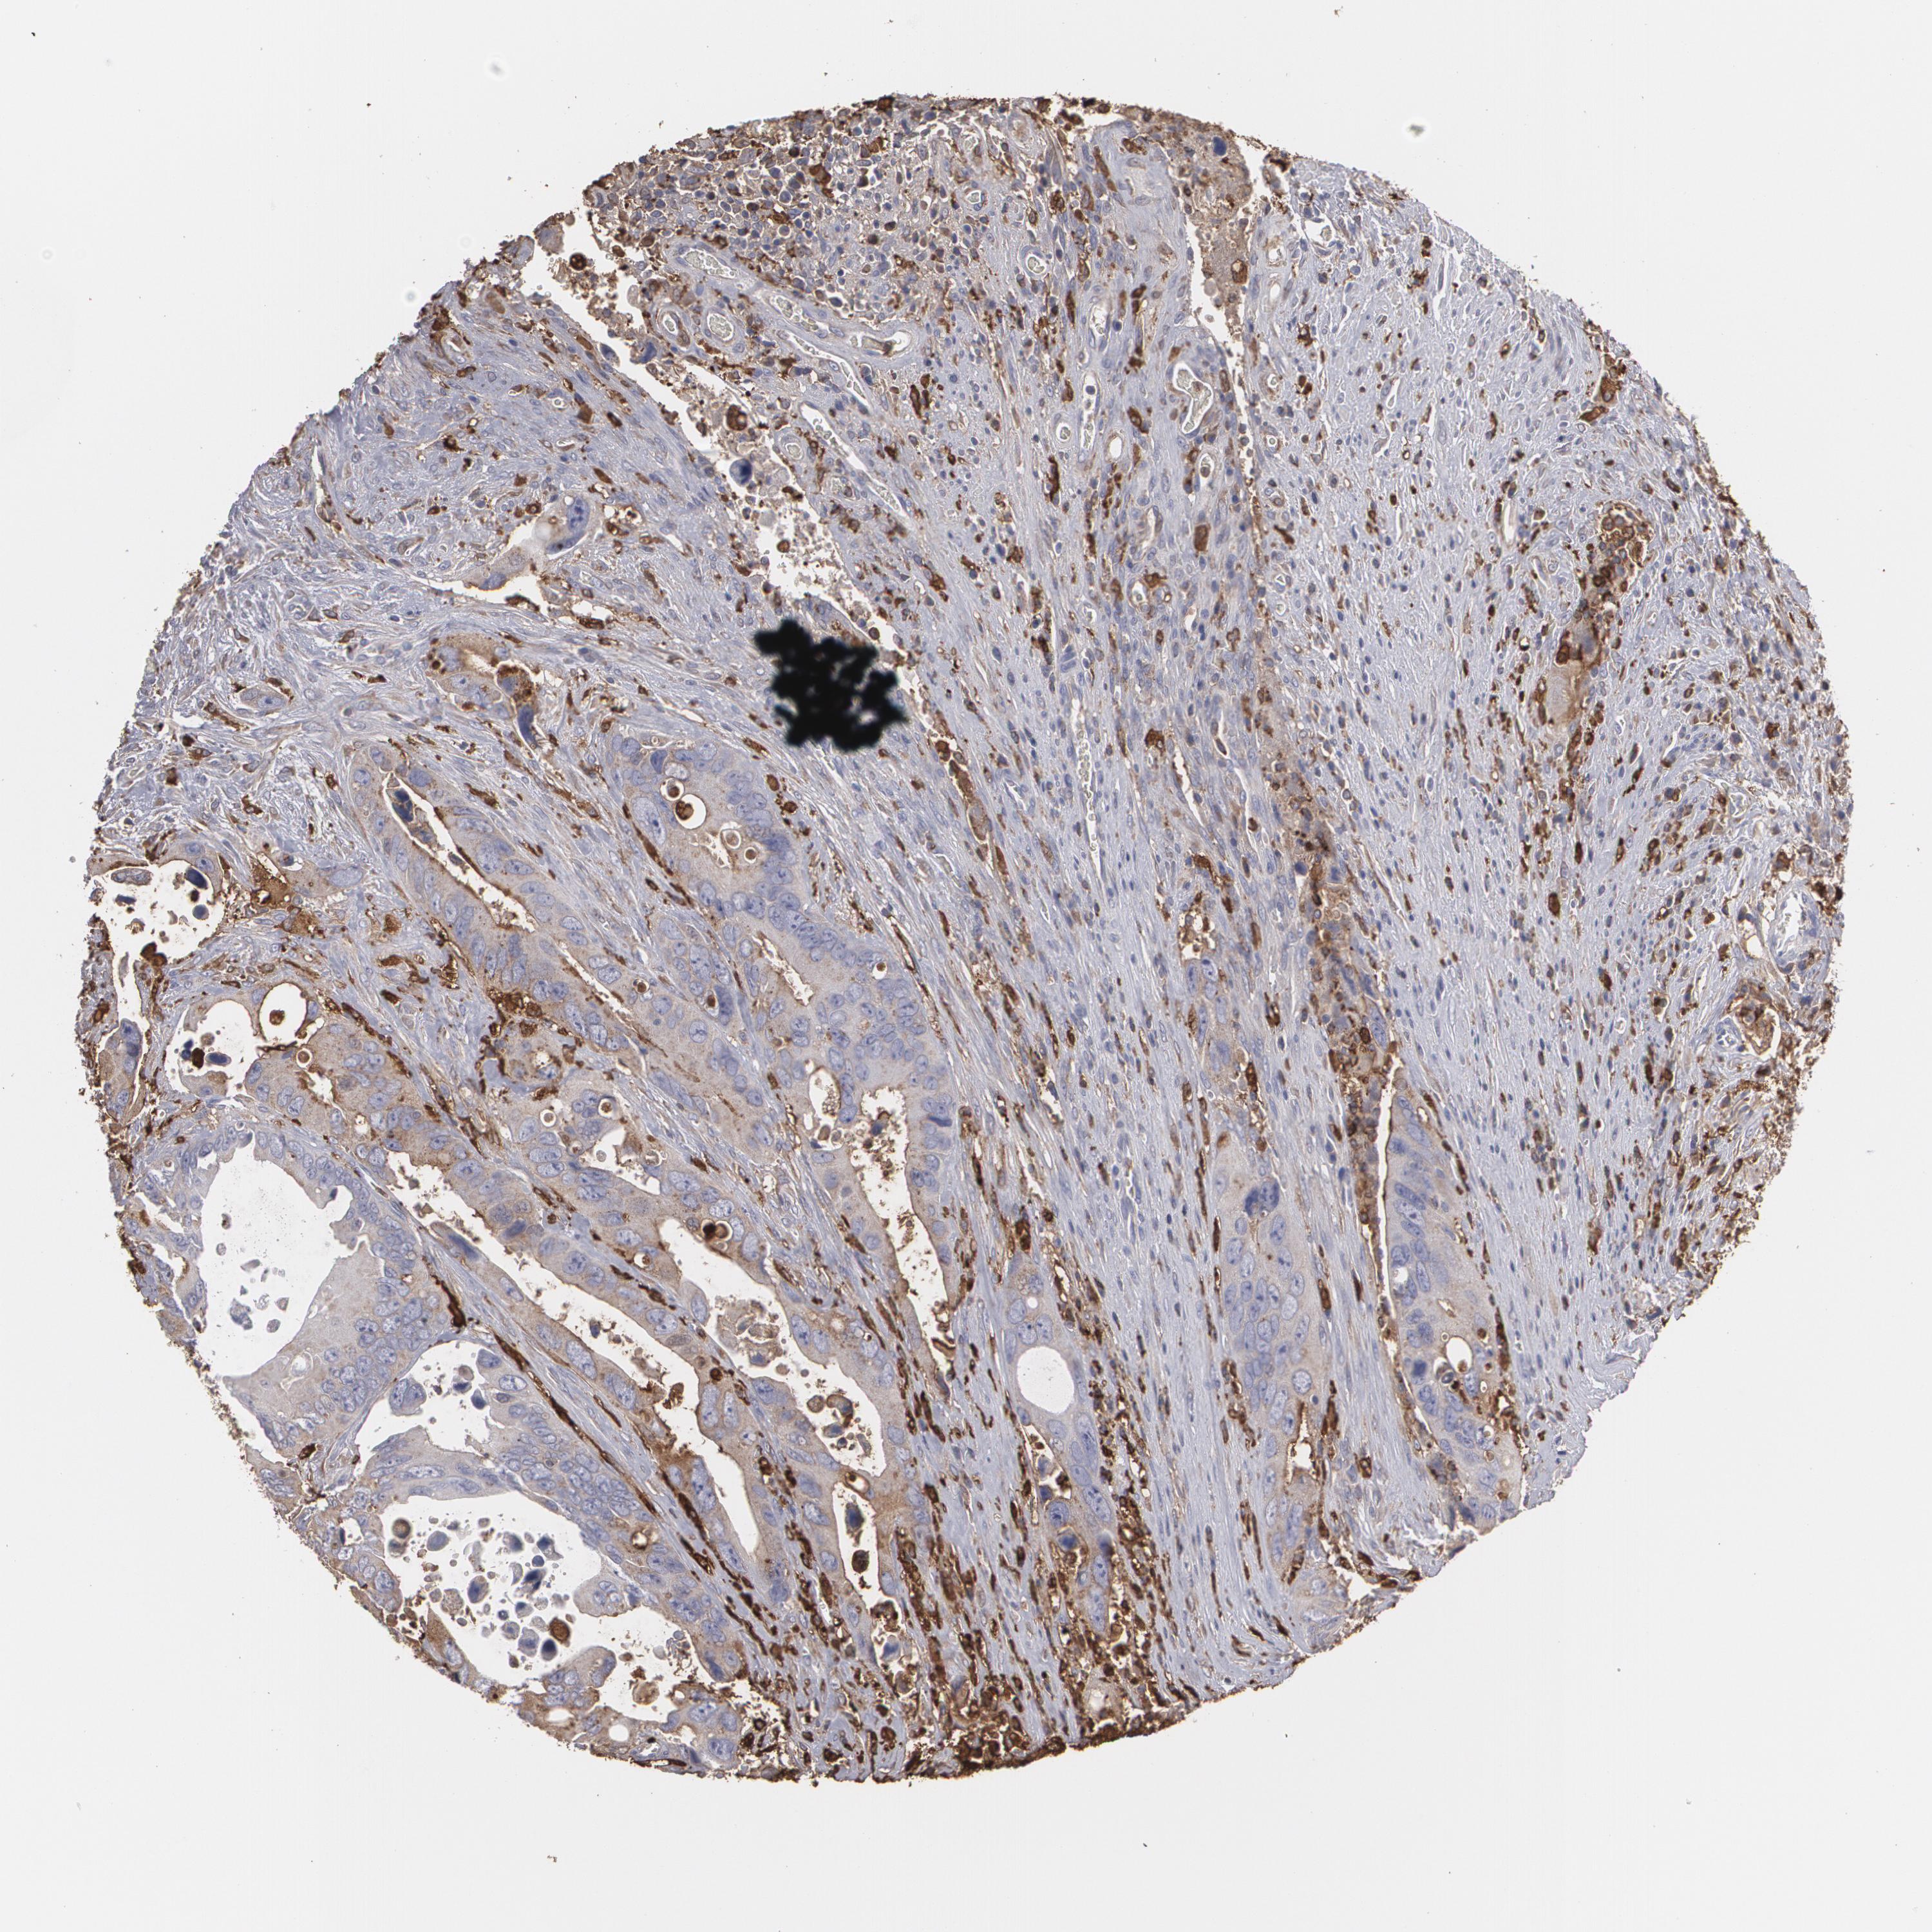

Colorectal cancer

Colon adenocarcinoma